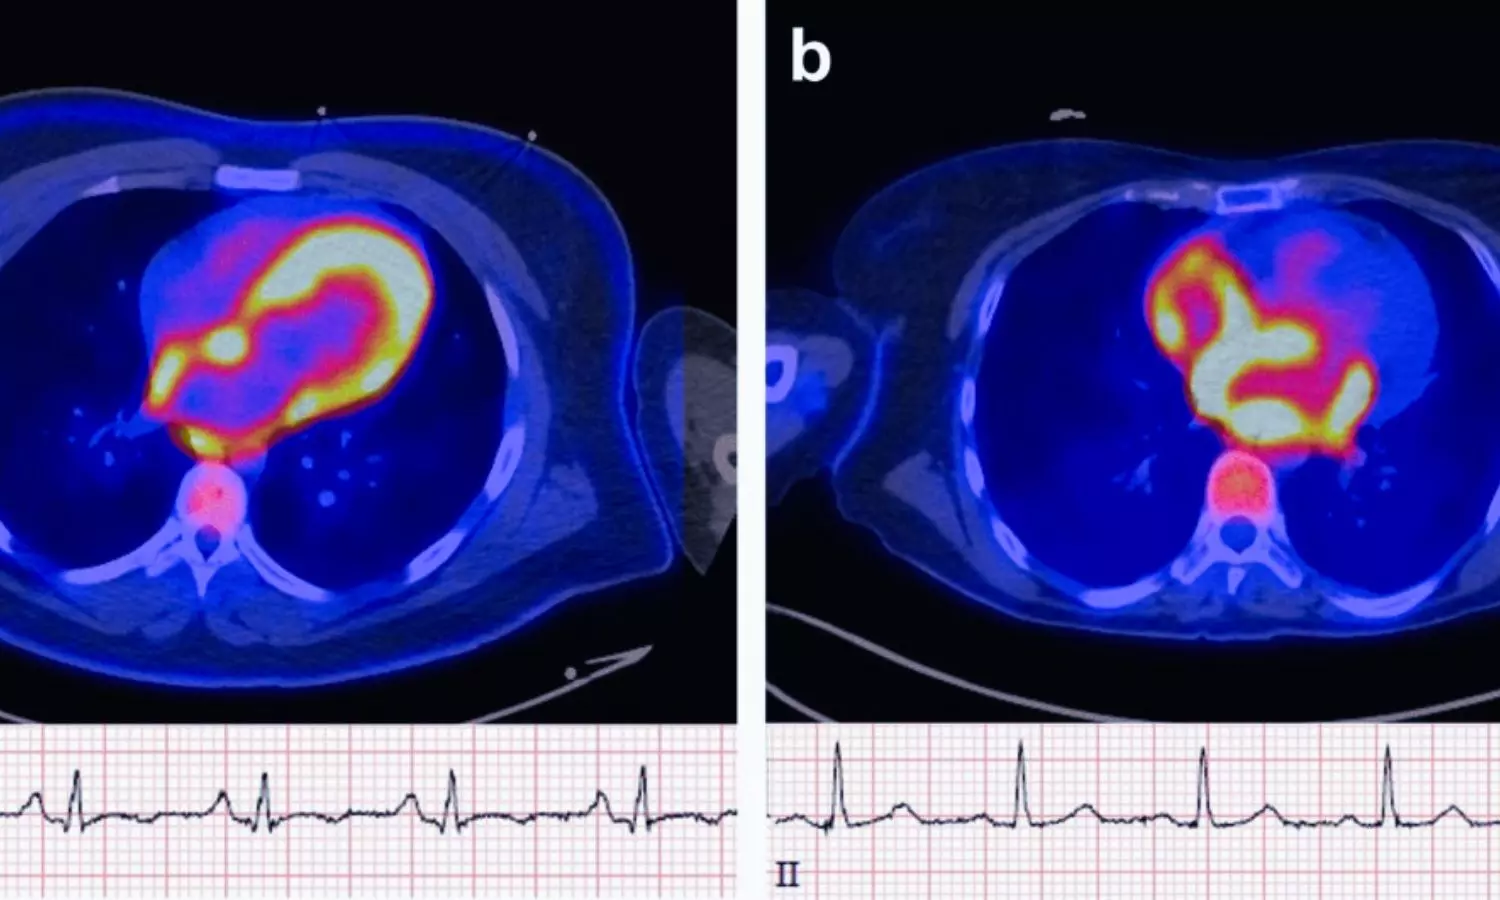

Atrial FDG Uptake on Cardiac PET Signals Higher Risk of Future Atrial Fibrillation: Study

USA: Positron emission tomography (PET) imaging may help identify patients at higher risk of developing atrial fibrillation (AF) by detecting increased metabolic activity in the atrial walls, a new study published on January 20 in JACC: Advances has found. The findings suggest that atrial uptake of the F-18 fluorodeoxyglucose (FDG) radiotracer is associated with a significantly higher likelihood of incident AF over long-term follow-up.

- Atrial FDG uptake was significantly more frequent in patients who developed AF than in those who did not.

- FDG uptake was observed more often in the atria than in the ventricles.

- Uptake was predominantly localized to the right atrium rather than the left atrium or both atria.